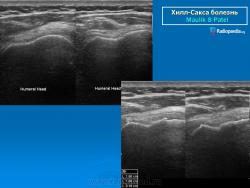

рентгенограмма плечевого сустава. Повреждение Хилл-Сакса и сопутствующий кальциноз сухожилий вращательной манжеты